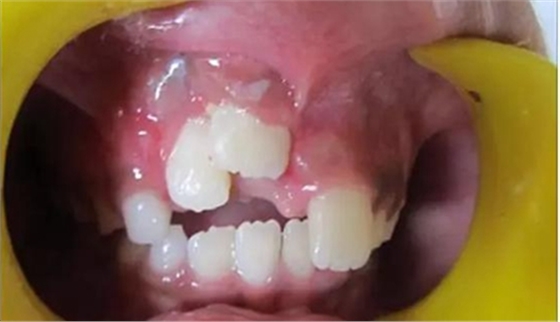

健康的 7 歲男童,前一天摔倒,上頜右中切牙和右側(cè)切牙發(fā)生挫入脫位(圖 1)。無牙外傷史,無神經(jīng)并發(fā)癥病史。檢查發(fā)現(xiàn)雙側(cè)下頜下腺增大。

口腔內(nèi)發(fā)現(xiàn):混合牙列早期,覆蓋正常,安氏I類磨牙關(guān)系。牙11和12齦緣紅腫。

牙11,12 和21對叩診敏感。牙11嚴(yán)重挫入(牙11和牙12的切緣相差7毫米),并挫入牙槽窩。與牙21相比,牙12大約挫入4毫米。

診斷:牙11嚴(yán)重挫入,牙12中度挫入,牙21震蕩傷。